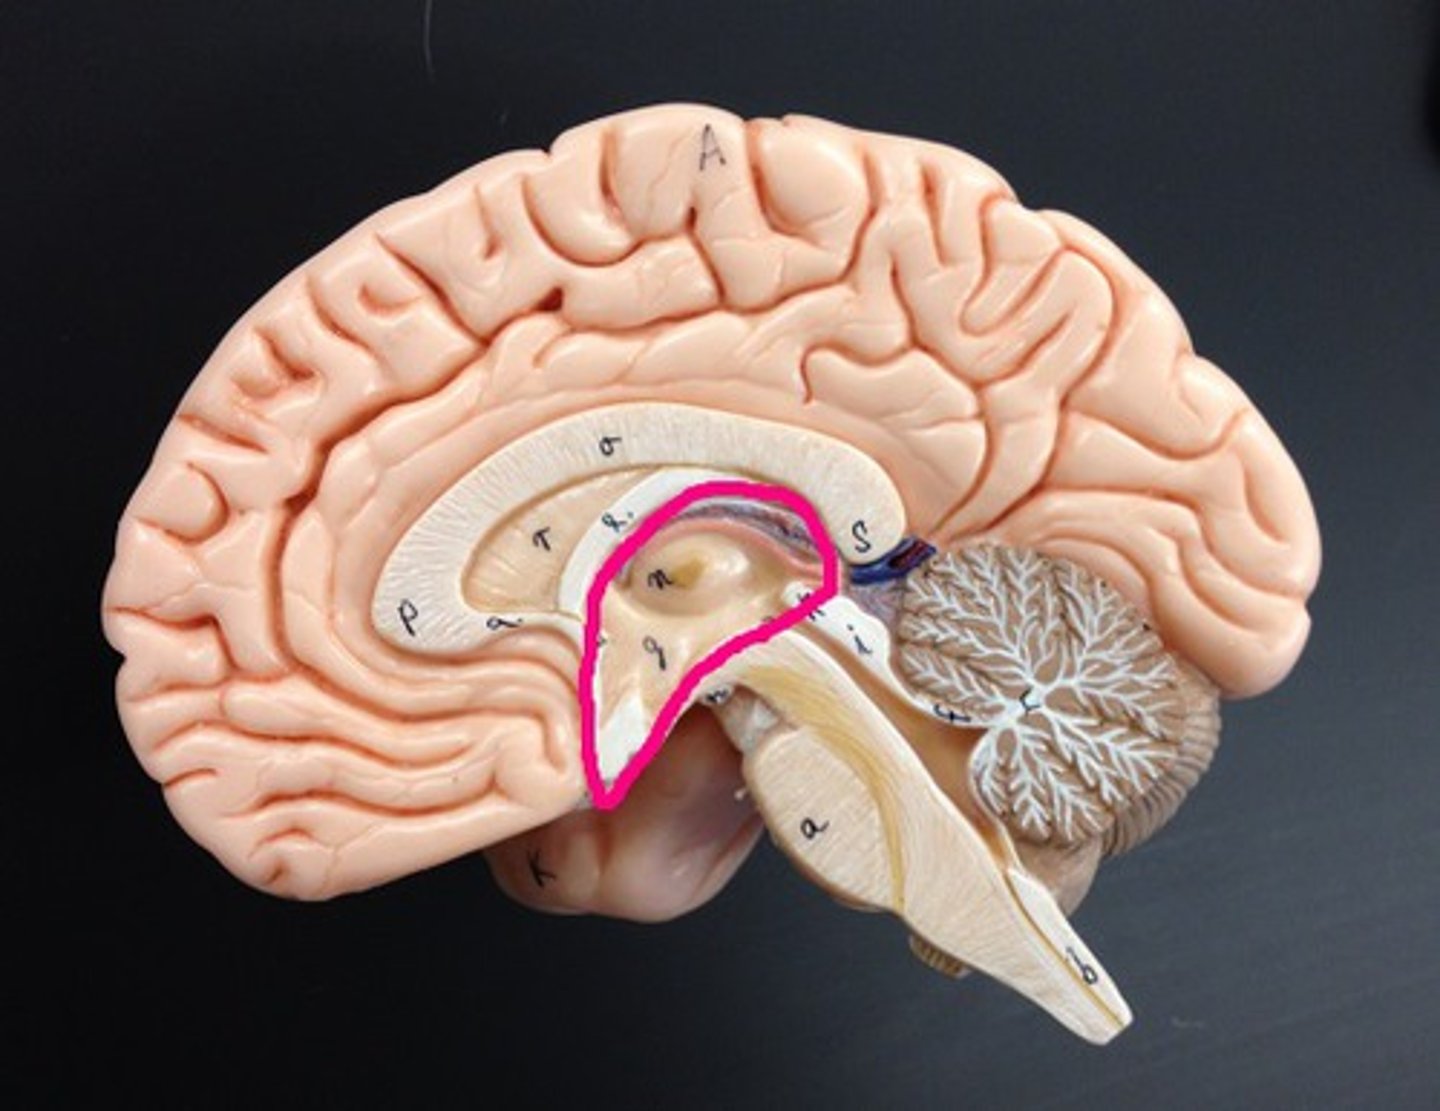

Ventricles

1) Right & left lateral ventricles:

-Anterior, Posterior & inferior horns

2) 3rd Ventricle, Cerebral aqueduct, 4th ventricles

4) Apertures (Narrow openings) into subarachnoid space of spinal cord

Anterior Horns

Posterior Horns

Inferior Horns

3rd Ventricle

4th Ventricle